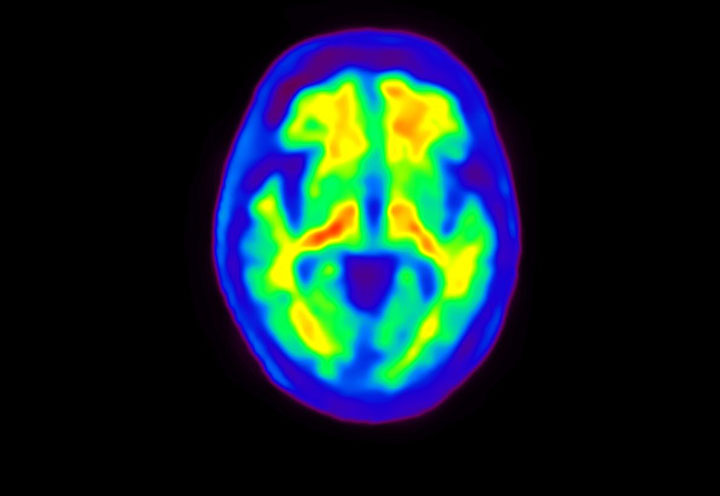

Head / Case4 : Amyloid

Axial

Courtesy : Kindai University Hospital

- Imaging protocol

- Injected dose: 3.21 MBq/kg, 18F-Flutemetamol

- Uptake time: 100 minutes

- Scan time: 20 minutes